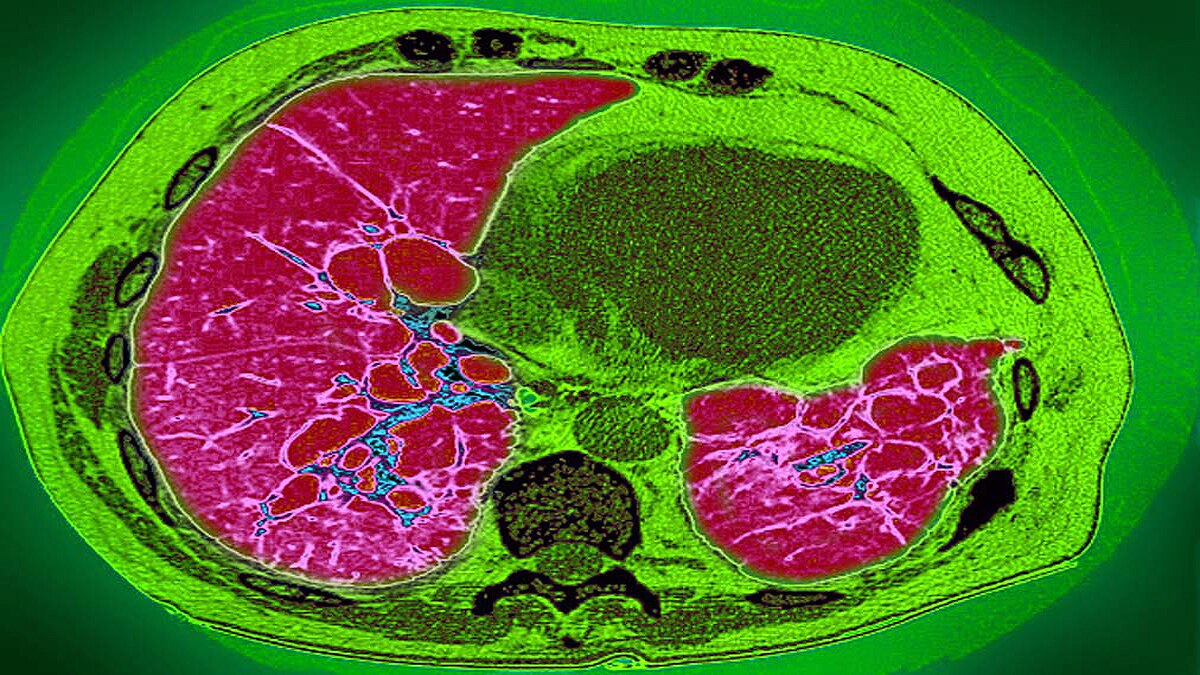

फेफड़ों के ऊतक सूज जाते हैं. ऑक्सीजन की कमी हो जाती है. ऐसे में खून का बहाव शरीर में कम होने लगता है. दिल ढंग से काम नहीं करता. नतीजा मल्टी ऑर्गन फेल्योर, हार्ट अटैक या गंभीर अवस्था में मौत भी हो सकती है. डॉ. उदवादिया कहते हैं कि मुझे उम्मीद है कि ज्यादातर लोग लंग फाइब्रोसिस (Lung Fibrosis) से ठीक हो सकते हैं लेकिन कुछ लोगों में यह बीमारी घर कर जाएगी. (फोटोः गेटी)

डॉ. उदवादिया कहते हैं कि ज्यादा समय तक अगर लंग फाइब्रोसिस (Lung Fibrosis) किसी मरीज में रहता है तो उसे श्वसन प्रणाली से संबंधित गंभीर बीमारियां लंबे समय के लिए हो सकती है. या फिर स्थाई तौर पर फेफड़ों की बीमारियों से ग्रसित हो सकता है. बीमारी का इलाज तो है लेकिन सबसे बड़ा इलाज है बचाव. (फोटोः गेटी)